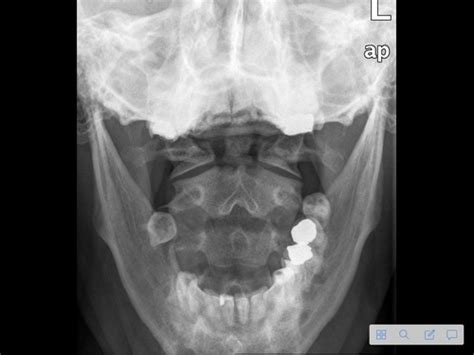

Okay, let’s get down to the nitty-gritty and look at some common OSCE scenarios you might encounter. Respiratory cases are a frequent one, so be ready to tackle asthma exacerbations, pneumonia, and COPD. You’ll need to demonstrate your ability to assess breath sounds, interpret chest X-rays, and manage respiratory distress. Practice your inhaler techniques and be prepared to educate patients on proper medication use. Cardiovascular scenarios often involve chest pain, heart failure, and hypertension. Master your cardiac examination skills, including auscultation for murmurs and palpation for peripheral edema. Know your ECG interpretation and be familiar with common cardiac medications. Gastrointestinal cases might include abdominal pain, gastrointestinal bleeding, and liver disease. You should be able to perform a thorough abdominal examination, identify signs of ascites, and interpret liver function tests. Don’t forget to ask about bowel habits and dietary history.

Neurological scenarios could involve stroke, seizures, and headaches. Practice your neurological examination skills, including assessing cranial nerves, motor strength, and sensory function. Know the Glasgow Coma Scale and be familiar with common neurological medications. Musculoskeletal cases often involve joint pain, back pain, and fractures. You should be able to perform a musculoskeletal examination, assess range of motion, and interpret X-rays. Be prepared to discuss management options, including pain relief and rehabilitation. Endocrine scenarios might include diabetes, thyroid disorders, and adrenal insufficiency. You’ll need to demonstrate your ability to assess blood glucose levels, interpret thyroid function tests, and manage hormonal imbalances. Practice your patient education skills, especially regarding insulin administration and dietary modifications.